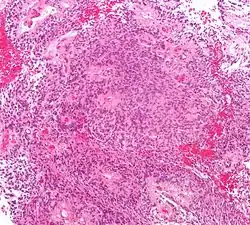

В типичных случаях на МРТ эпендимомы видны в виде объёмных образований, которые заполняют, а иногда и полностью тампонируют полость IV желудочка и распространяются в большую затылочную цистерну или боковую цистерну моста. Солидная часть новообразования на Т1-взвешенных томограммах выглядит изо- или даже гипоинтенсивной и гиперинтенсивной на Т2-взвешенных томограммах[24].

Дифференциальная диагностика эпендимом с другими глиомами основывается в основном на их локализации и топографии, а не на различиях интенсивности сигнала или степени контрастного усиления[25]. Кистозный компонент имеет гипоинтенсивный сигнал на Т1-взвешенных МРТ и гиперинтенсивный по отношению к мозгу на изображениях, взвешенных по Т2. Гетерогенность структуры опухоли обусловлена наличием кист, петрификатов, опухолевой сосудистой сети. После введения контраста отмечается негомогенное усиление средней интенсивности[26]. Дифференциальную диагностику эпендимом боковых желудочков необходимо проводить с медуллобластомами и астроцитомами[23].

Анапластические эпендимомы отличаются более выраженной гетерогенностью сигнала, нечёткостью границ, большим распространением, интенсивным накоплением контраста и наличием зон некроза[24].